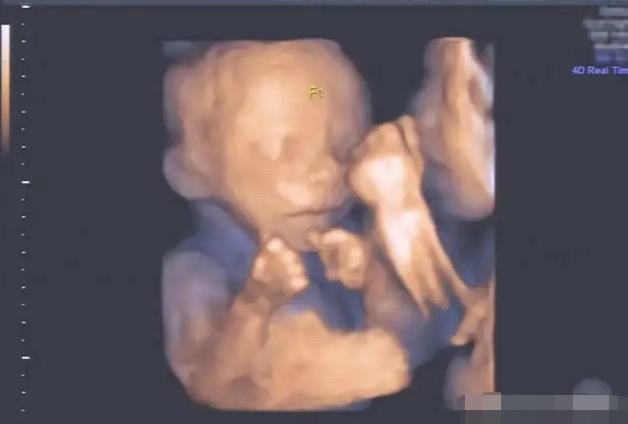

琪琪今年怀孕了,经过医生的检查后,证实琪琪怀的是三胞胎,这让身边的亲戚朋友很是羡慕。

但是怀了5个月后,在一次琪琪去医院产检回来后,全家人就开始闷闷不乐了。原来是因为琪琪产检时,医生通过观察发现,这三胞胎可能是连体婴儿,建议琪琪引产。

令人欣喜的是这三名宝宝并不是连体婴儿,而是单独的、独立的个体。

医生也是震惊的,当时检查出连体婴儿的医生表示可能是由于胎儿的体位导致、或可能是当时两个宝宝抱在了一起,所以给医生一种是连体婴儿的错觉。